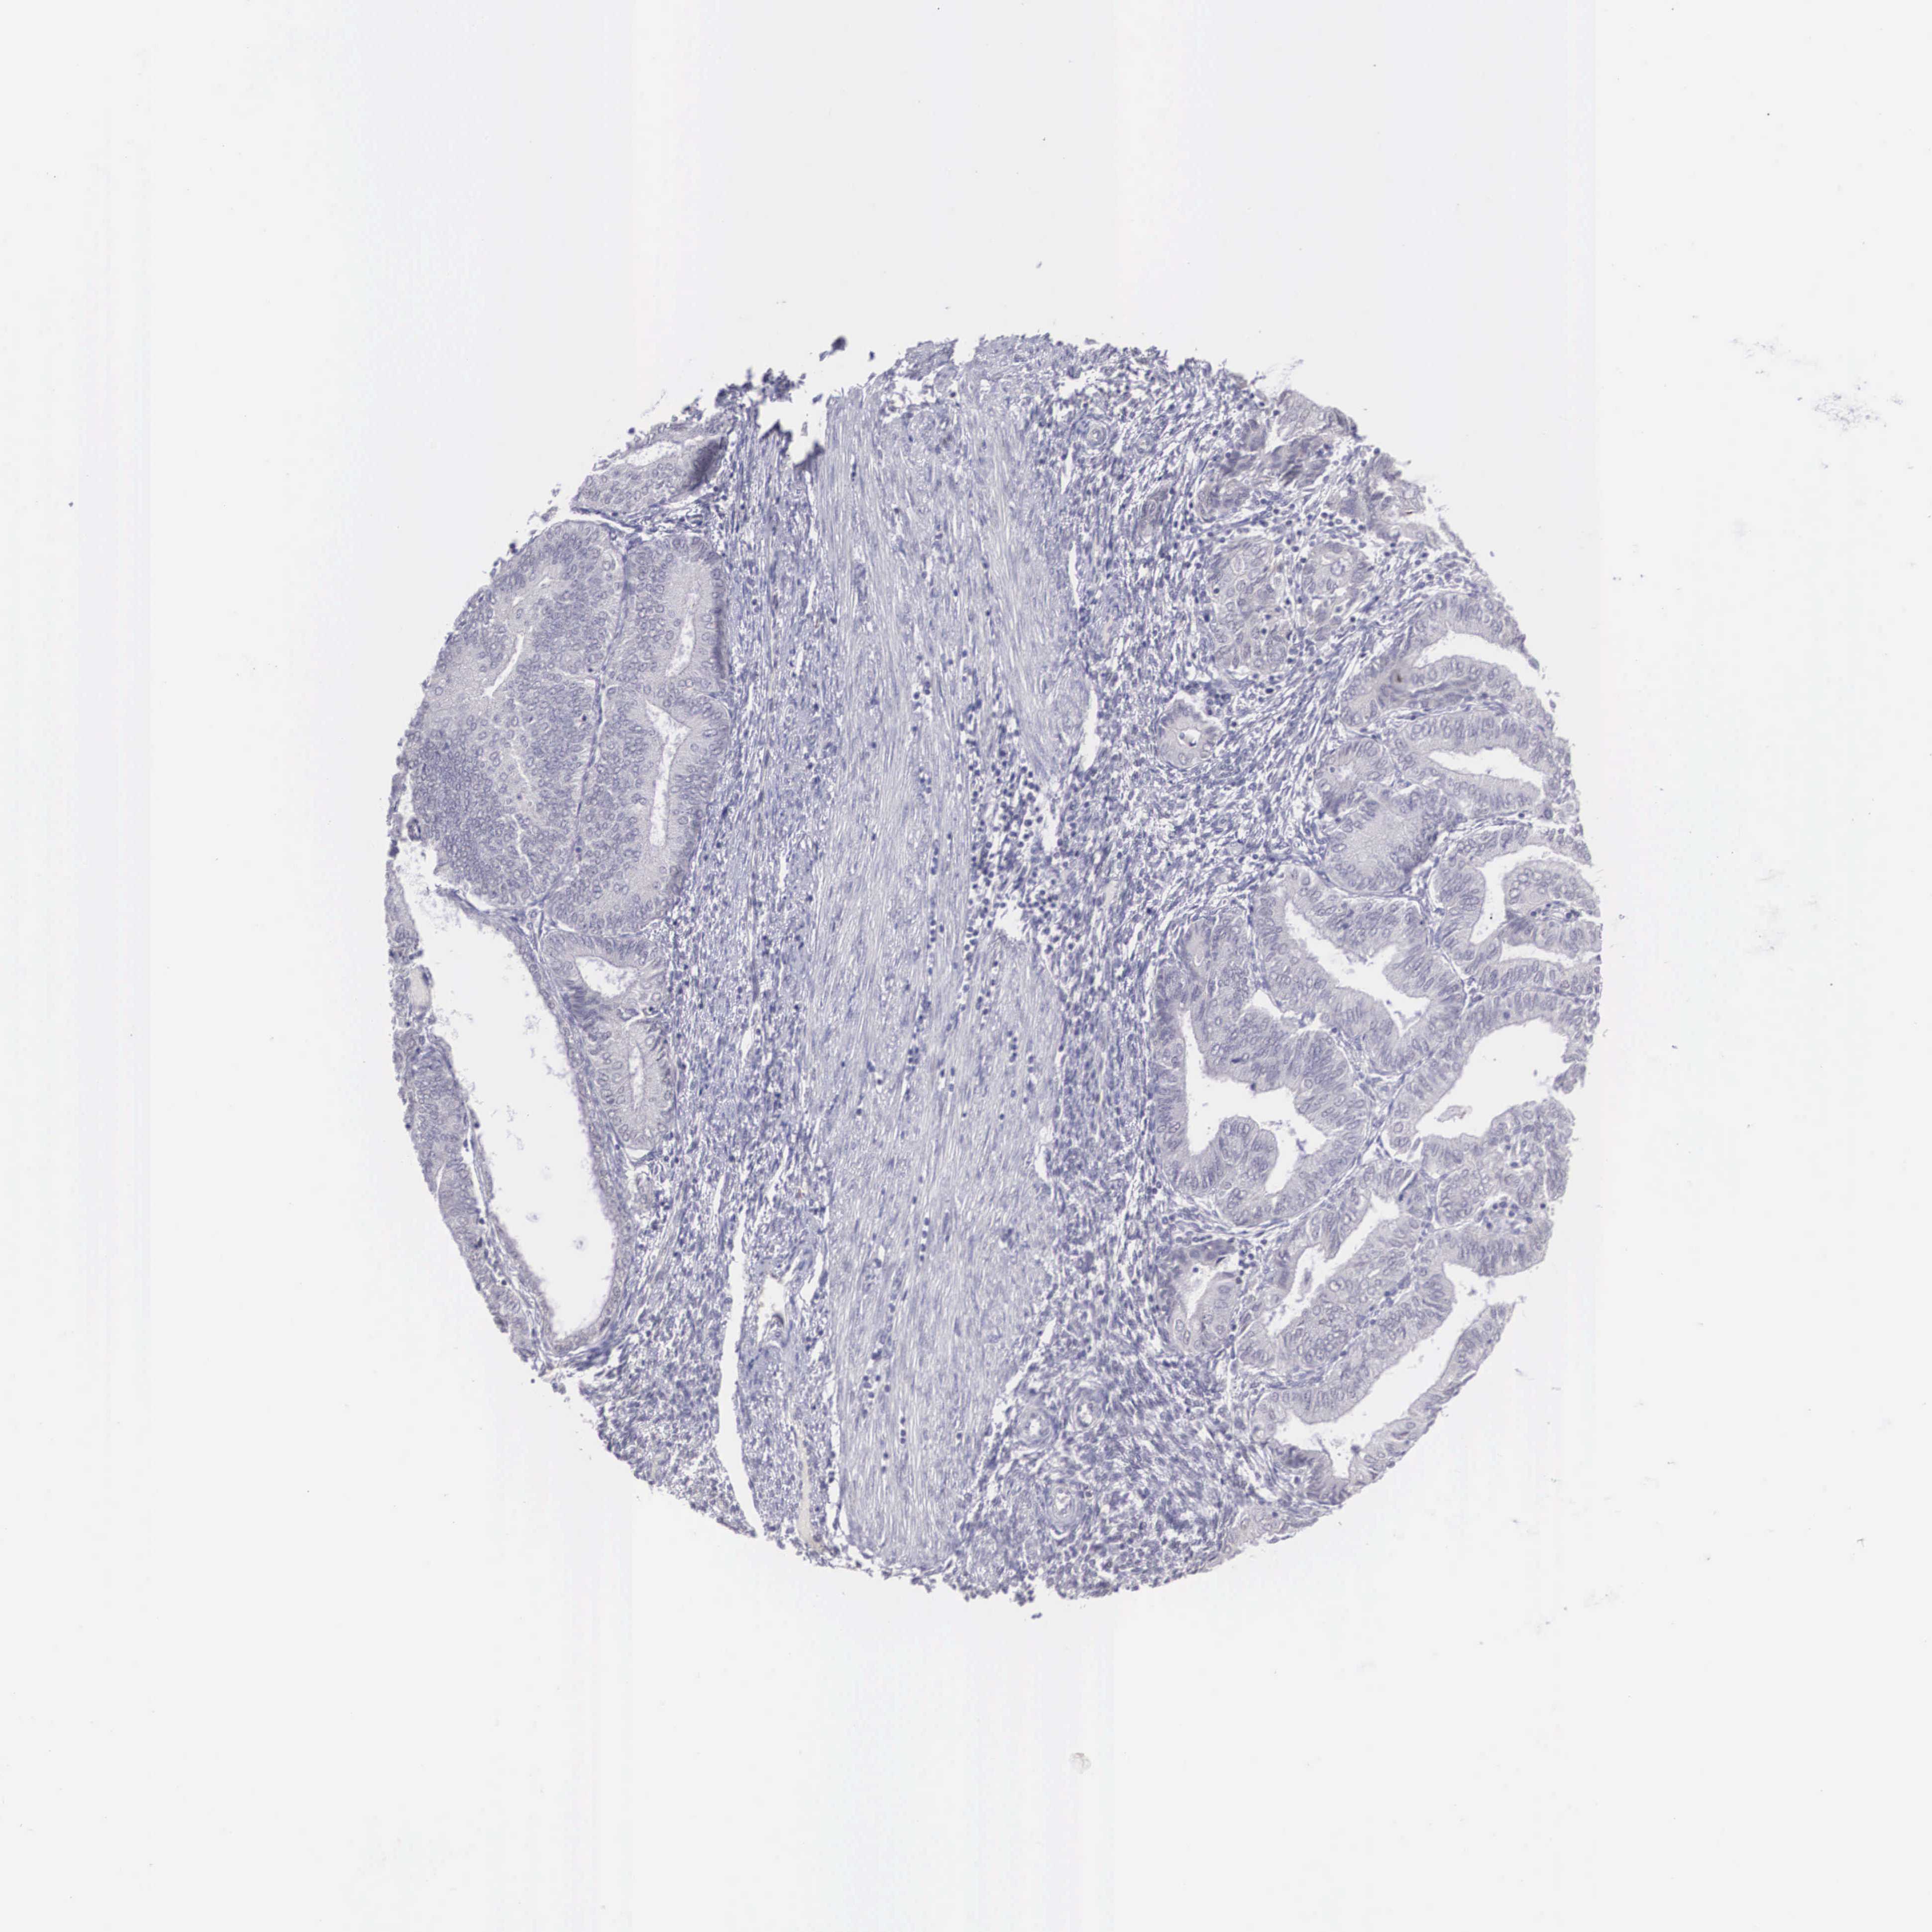

ENDOMETRIAL CANCER - Protein expressioni

A mouse-over function shows sample information and annotation data. Click on an image to view it in a full screen mode. Samples can be filtered based on level of antibody staining by selecting one or several of the following categories: high, medium, low and not detected. The assay and annotation is described here.

Note that samples used for immunohistochemistry by the Human Protein Atlas do not correspond to samples in the TCGA dataset.

Antibody stainingi

Antibody staining in the annotated cell types in the current human tissue is reported as not detected, low, medium, or high, based on conventional immunohistochemistry profiling in selected tissues. This score is based on the combination of the staining intensity and fraction of stained cells.

Each image is clickable and will lead to virtual microscopy that enables deeper exploration of all samples and also displays staining intensity scores, fraction scores and subcellular localization as well as patient and tissue information for each sample.

Antibody HPA000686

Staining

High

Medium

Low

Not detected

Intensity

Strong

Moderate

Weak

Negative

Quantity

>75%

75%-25%

<25%

None

Location

Nuclear

Cytoplasmic/membranous

Cytoplasmic/membranous,nuclear

Adenocarcinoma, NOS